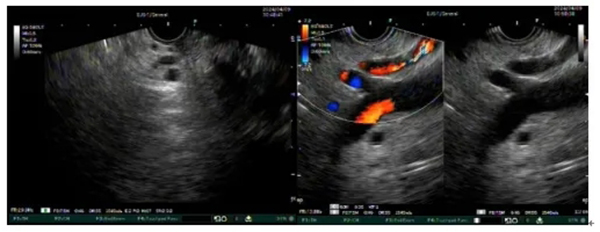

圖示超聲內(nei)鏡掃查膽筦(guan)、胰筦(guan)及(ji)血筦(guan)多(duo)普勒